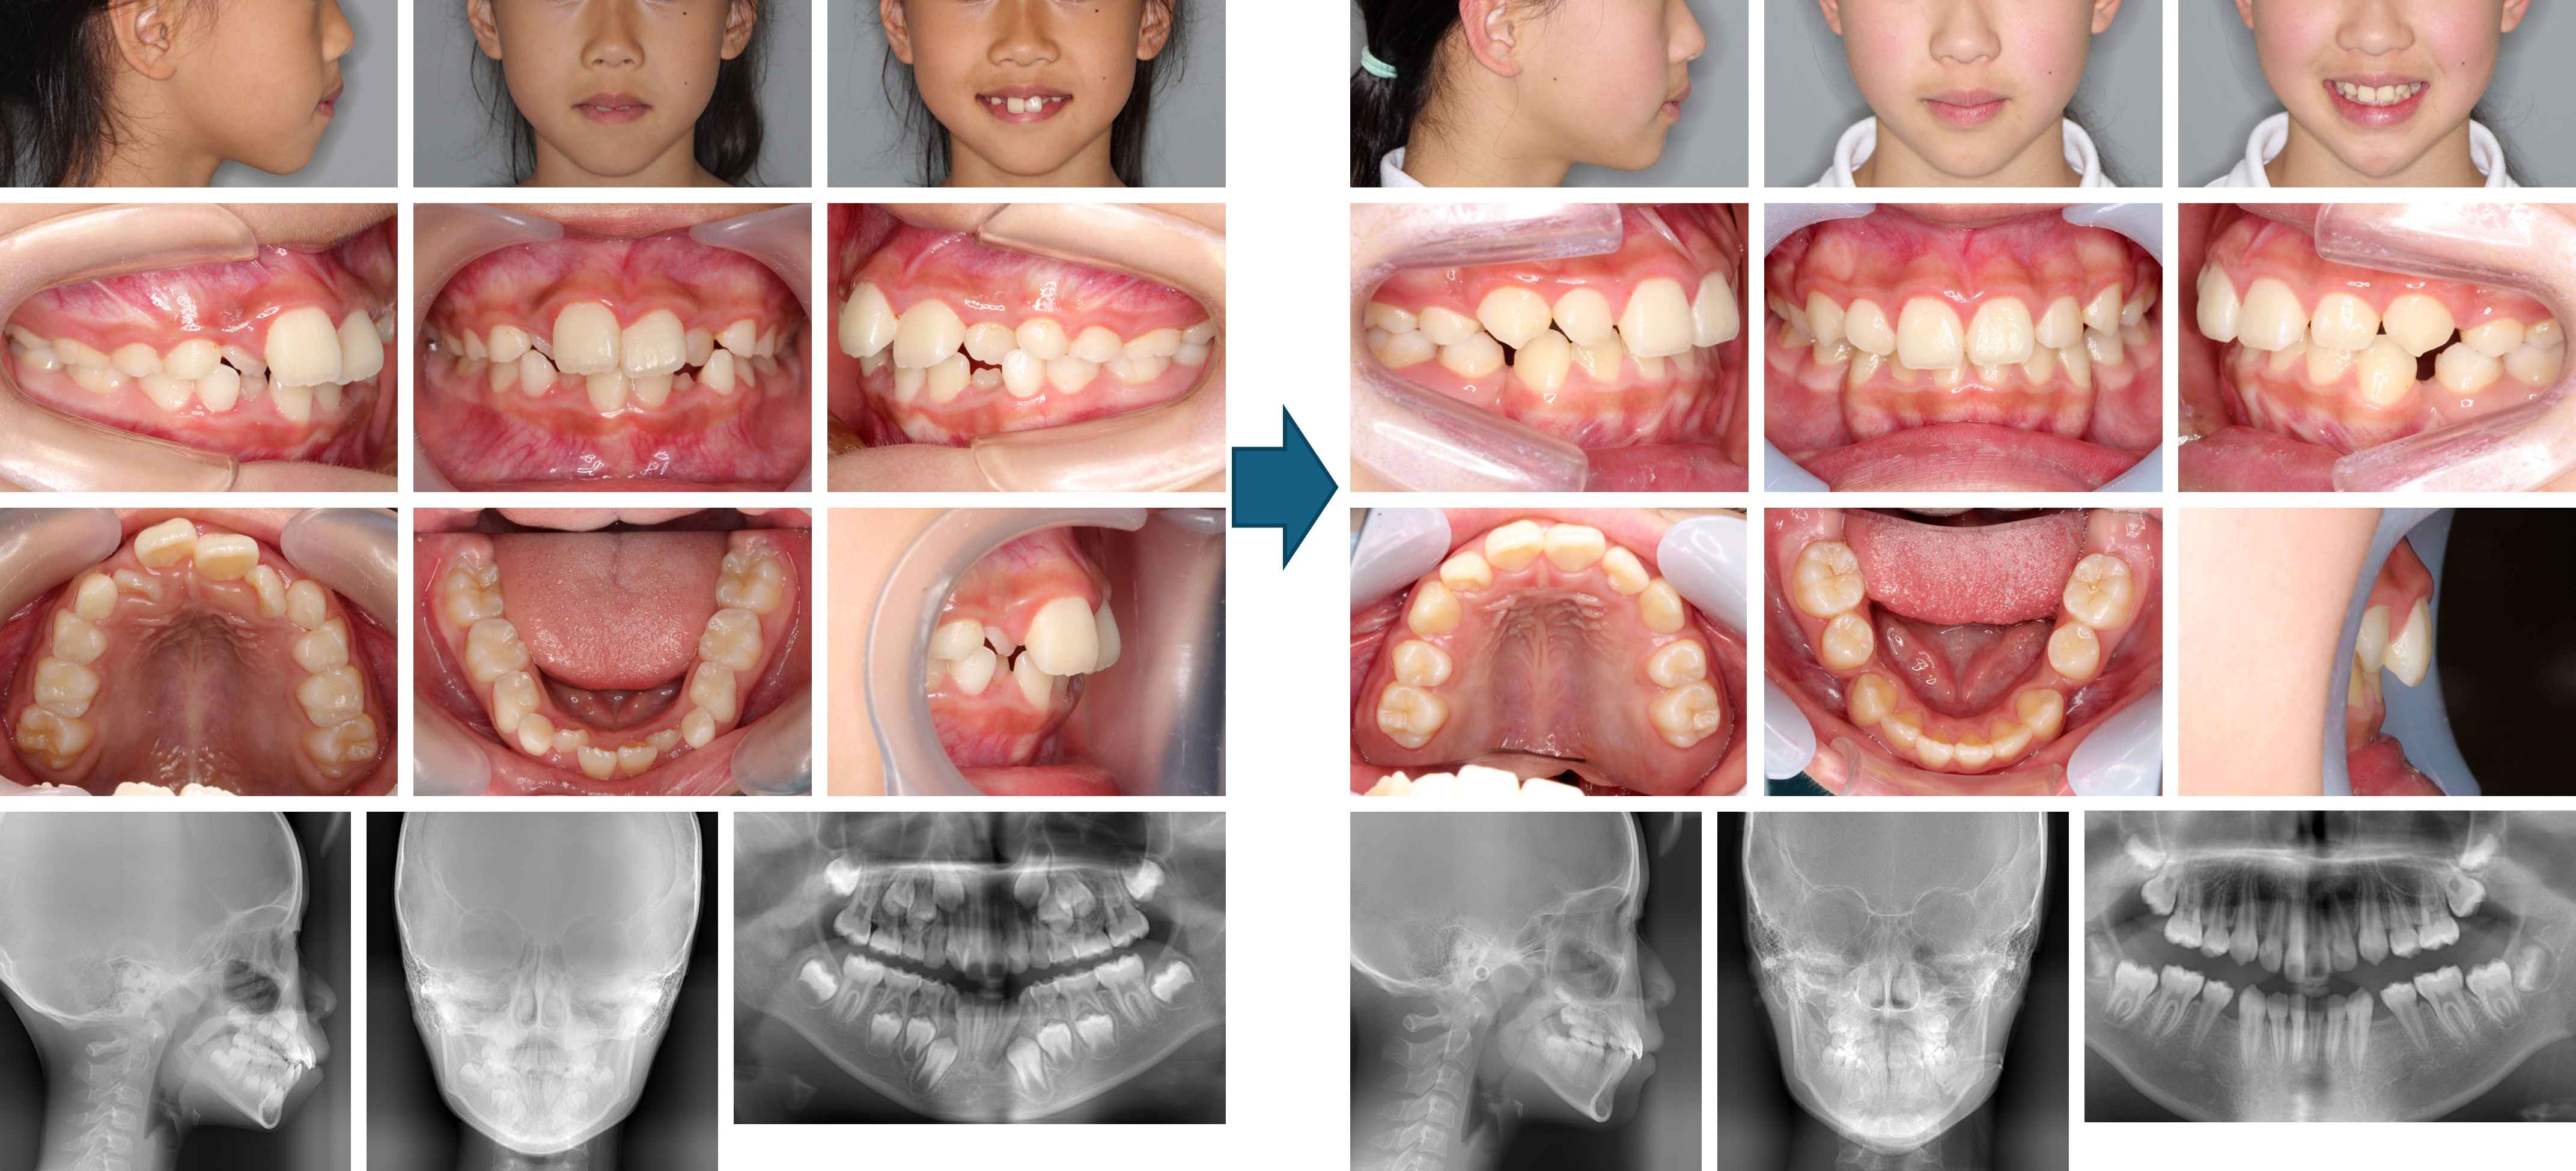

【治療例 K5284】初診時年齢:6歳11か月 / 性別:女性 / 主訴:前歯の咬み合わせ

治療の概要:第1期治療ではクワドヘリックスで側方拡大および右側中切歯の反対咬合の改善を行いながら、前方牽引装置で上顎骨の前方成長を促しました。2×4装置で上顎前歯部を綺麗に並べた後、しばらく永久歯の萌出を待ちました。側方歯の永久歯の萌出後、第2期治療では残りの永久歯にマルチブラケット装置を装着しました。綺麗な相貌と緊密な咬合を獲得しました。

主訴:前歯の咬み合わせ

診断名:上顎骨劣成長を伴う骨格性Ⅲ級、右側中切歯の反対咬合

使用した主な装置:クワドヘリックス、フェイスマスク、マルチブラケット装置、顎間ゴム

抜歯/非抜歯および抜歯部位: 非抜歯(ただし、乳歯の抜歯はあり)

※こちらの症例は2010年8月から2018年4月に行った矯正歯科治療ですが、消費税は10%で表示しております。

治療期間:5年8か月(第1期治療:2年1か月、 第2期治療:3年7か月)

治療回数:第1期治療13回、第2期治療61回